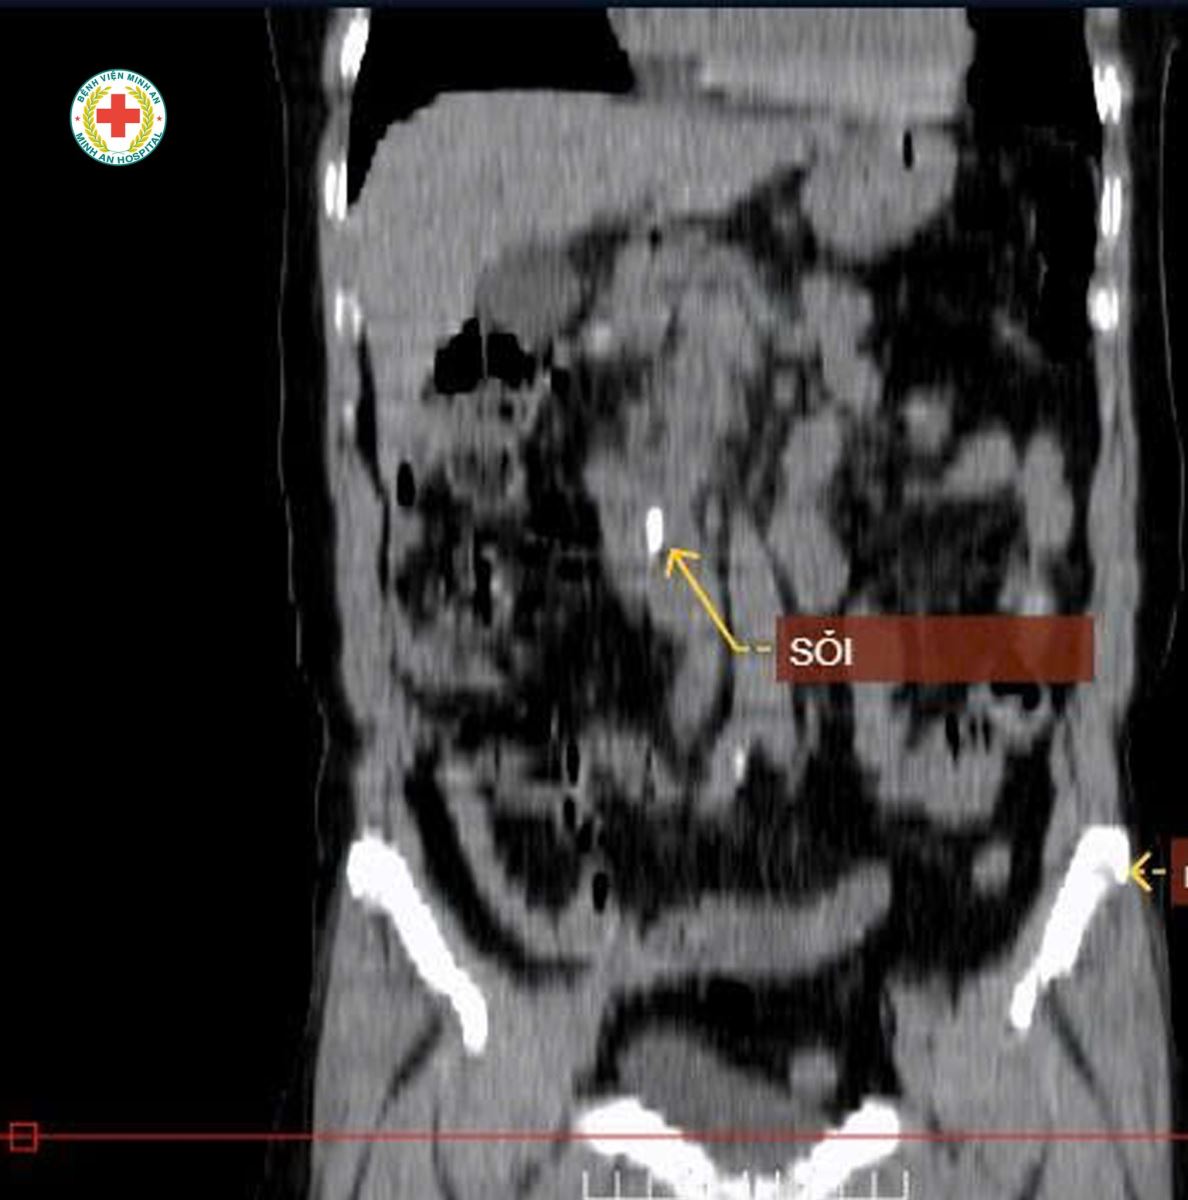

CT Scanner phát hiện giãn đường mật trong và ngoài gan do sỏi bóng Vater

Chẩn đoán xác định: SỎI ỐNG MẬT CHỦ GÂY TẮC MẬT

Người bệnh được chỉ định nội soi can thiệp mật tụy ngược dòng (ERCP), lấy thành công viên sỏi kích thước 12 × 7,5 mm, giải phóng tắc mật, giúp triệu chứng cải thiện nhanh chóng và rút ngắn thời gian điều trị